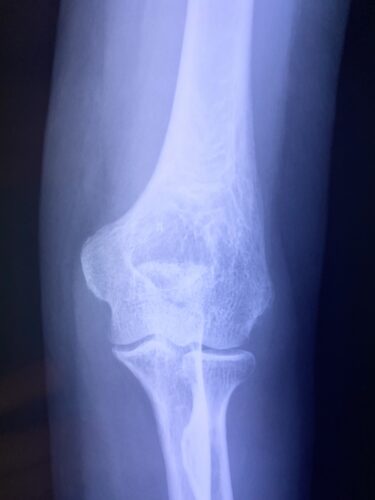

春日部市市民活動センター(肘関節脱臼)

春日部市市民活動センター(上腕骨顆上骨折)

第28回整骨研究会「賜恩」研修会開催

小児上腕骨外顆回転骨折の1症例について

肘関節前方脱臼の1症例について